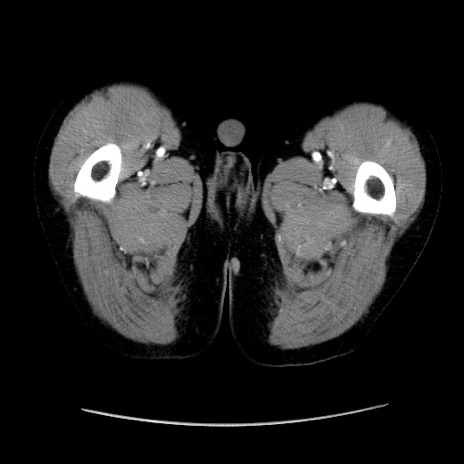

症例37(横断像)

【症例】40歳代 男性

【主訴】腹痛

【現病歴】4時間ほど前に電車に乗車中に臍部上より腹痛出現。徐々に増悪し起立困難となり、救急外来受診。生ものは数日食べていない。今朝お雑煮を食べた。

【身体所見】BT 36.8℃、BP 117/84mmHg、HR 91/min、SpO2 97%、苦悶様、腹部:臍上部広範囲圧痛あり、反跳痛±

【データ】WBC 8100、CRP 0.03